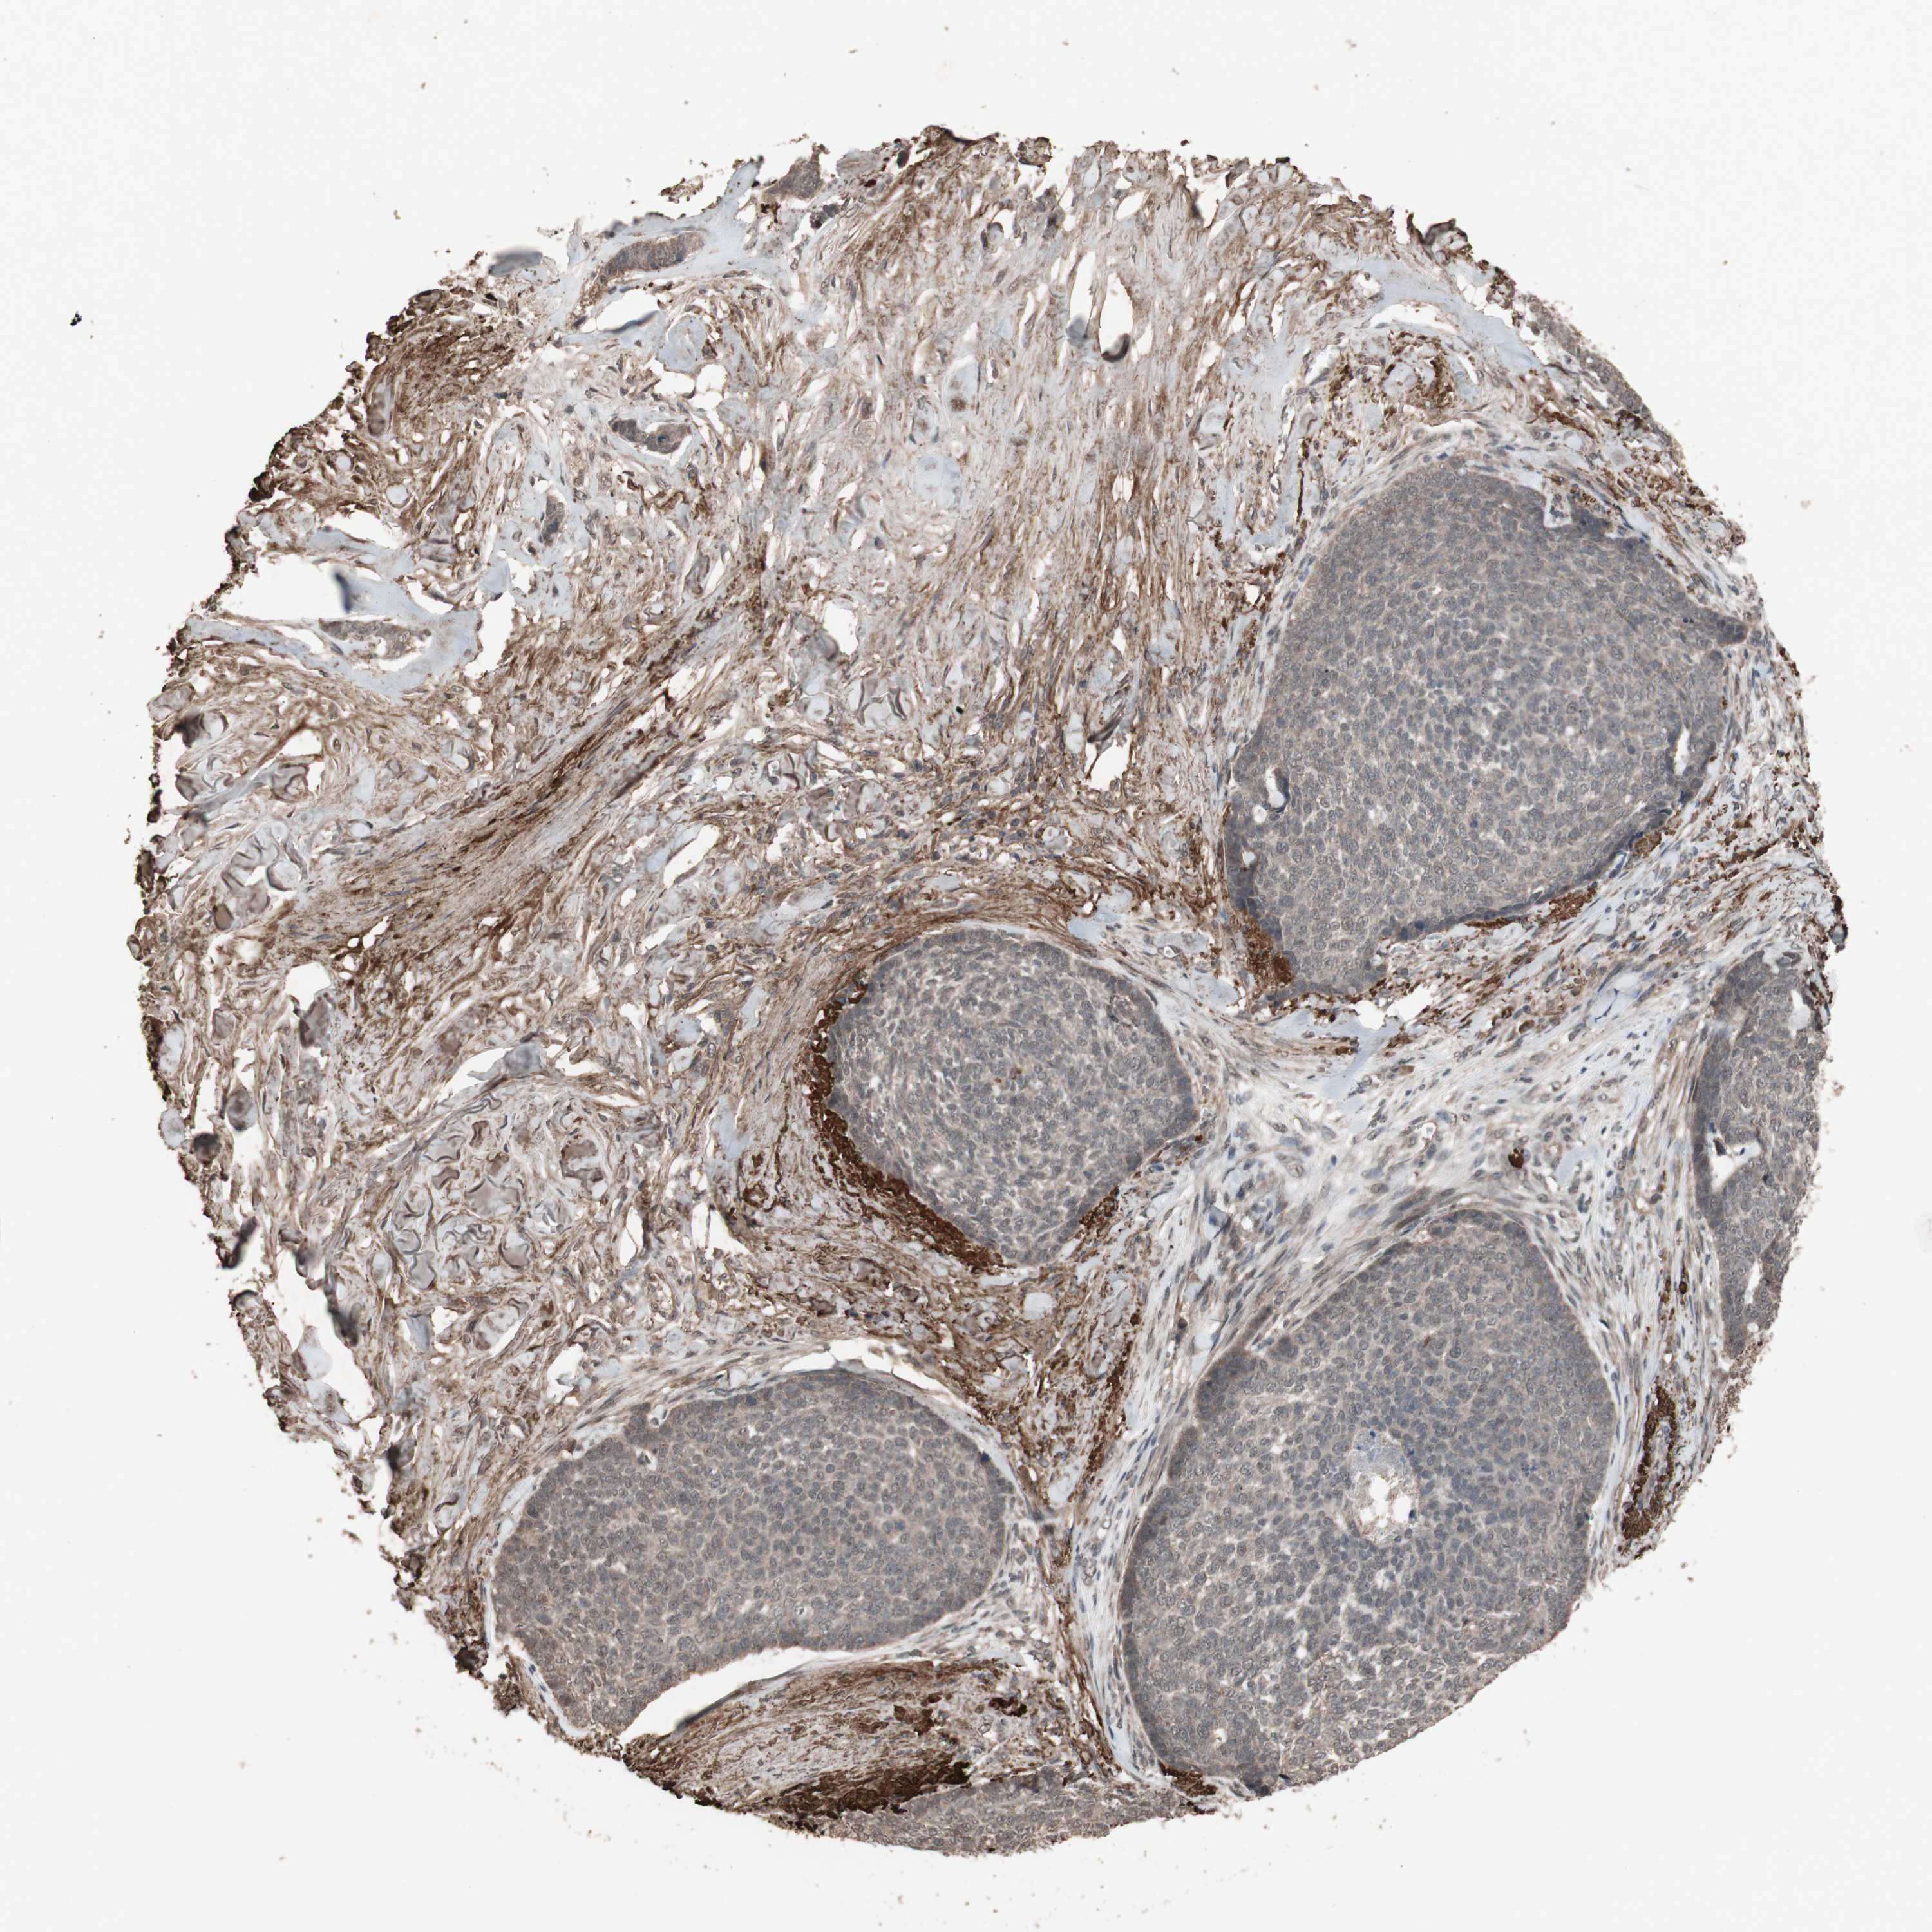

SKIN CANCER - Protein expressioni

A mouse-over function shows sample information and annotation data. Click on an image to view it in a full screen mode. Samples can be filtered based on level of antibody staining by selecting one or several of the following categories: high, medium, low and not detected. The assay and annotation is described here.

Each image is clickable and will lead to virtual microscopy that enables deeper exploration of all samples and also displays staining intensity scores, fraction scores and subcellular localization as well as patient and tissue information for each sample.

Antibody HPA006874

Antibody HPA007208

Staining

High

Medium

Low

Not detected

Intensity

Strong

Moderate

Weak

Negative

Quantity

>75%

75%-25%

<25%

None

Location

Nuclear

Cytoplasmic/membranous

Cytoplasmic/membranous,nuclear

Squamous cell carcinoma, NOS

Basal cell carcinoma